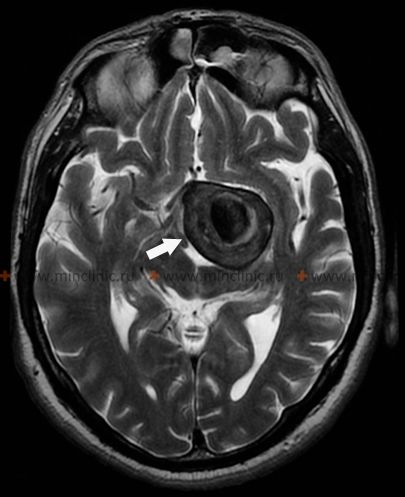

თავის ტვინის არტერიები გიგანტურ ანევრიზმებს (2,5 სმ-ზე მეტი დიამეტრით) იგივე ლოკალიზაცია აქვთ, რაც პატარა ანევრიზმებს. თავის ტვინის არტერიის გიგანტური ანევრიზმები ყველაზე ხშირად ლოკალიზებულია შიდა საძილე არტერიის ტვინშიდა ნაწილში, ტვინის შუა არტერიის ბიფურკაციაში და ძირითადი არტერიის მწვერვალზე. მიუხედავად იმისა, რომ მათი გახლეჩა შეუძლებელია, ასეთი ანევრიზმები ჩვეულებრივ იწვევენ ნევროლოგიურ სიმპტომებს ტვინზე ზეწოლის შედეგად ზომაში მომატების დროს.

გიგანტური ანევრიზმით კომპრესიის შემთხვევაში ტვინის შეშუპების განვითარება შეიძლება შეუქცევადი გახდეს და გამოიწვიოს ტვინის გამოხატული ზეწოლა და პაციენტის სიკვდილი. ასეთი შედეგი განსაკუთრებით მაშინაა მოსალოდნელი, თუ გიგანტური ანევრიზმა მდებარეობს ტვინის შუა არტერიის ბიფურკაციაში. ამ შემთხვევაში ნეიროქირურგიული ოპერაცია, რომელიც მიმართულია ტვინის დეკომპრესიისაკენ, მკურნალობის ერთადერთი ადეკვატური მეთოდია. მსგავსი ოპერაცია ტვინის არტერიის გიგანტური ანევრიზმის არსებობისას ტექნიკურად რთულად შესასრულებელია და ხშირად გართულებებს იწვევს ტვინის შეშუპების შემთხვევაში.